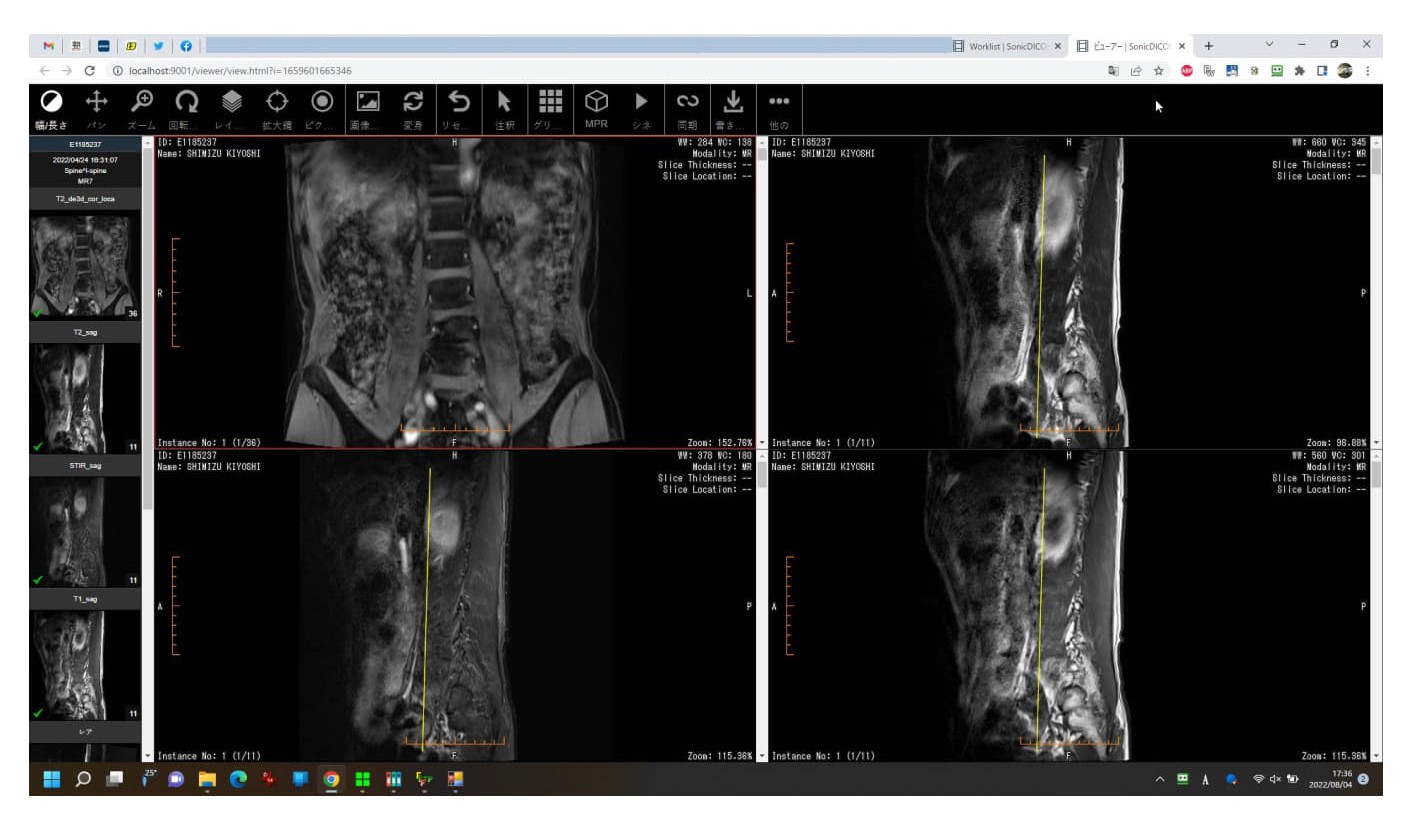

3. このビューワのタブはMiniRADMAXの画像表示画面に相当するもので、デフォルトでは2x2に分割されています。分割数を変えたい場合は、上部中央の■9個のアイコンを押して指定します。断面のスライスを切り替えたい場合は、その断面の画像をクリックした後、キーボードの↑↓を押すことで切り替えられます。

sonic DICOM procedure 2

SonicDICOM procedure 3

sonic DICOM procedure 4